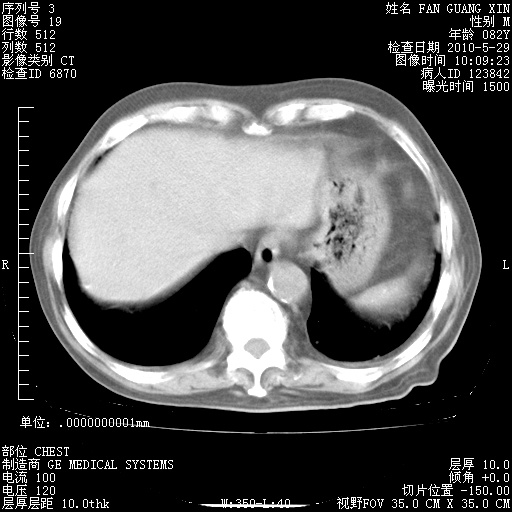

再治疗10天后的肺部CT

再治疗10天后的肺部CT 纵膈窗

阅读此次胸部CT,肺间质渗出性改变较入院时有吸收。目前从体温、白细胞、中性分叶明显增高,肯定存在细菌感染(发生医院感染哦,若无消化道及泌尿系统等感染的依据,肺部感染可能大)。若你院头孢哌酮舒巴坦钠耐药率较高,同意你的方案,若48小时体温仍高,可考虑使用碳青霉稀类抗菌药物,同时可予超声雾化、注意滴数时加大液体量。白蛋白33.30g/L较低哦,需加强营养等支持治疗。